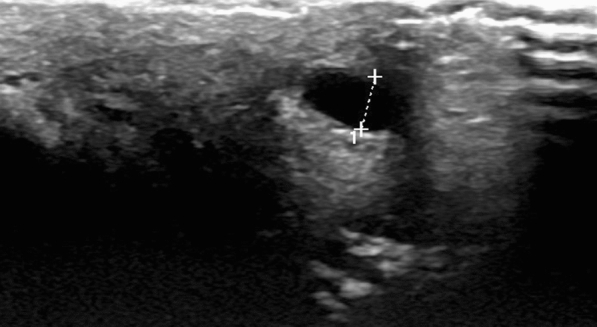

Superficial Doppler ultrasonography revealed dorsal induration consistent with segmental thrombosis of the superficial dorsal vein, suggestive of penile Mondor’s disease (Figs. 1, 2).

Fig. 1.

Ultrasonographic view of incompressible dilated superficial venous structure on dorsum of penis